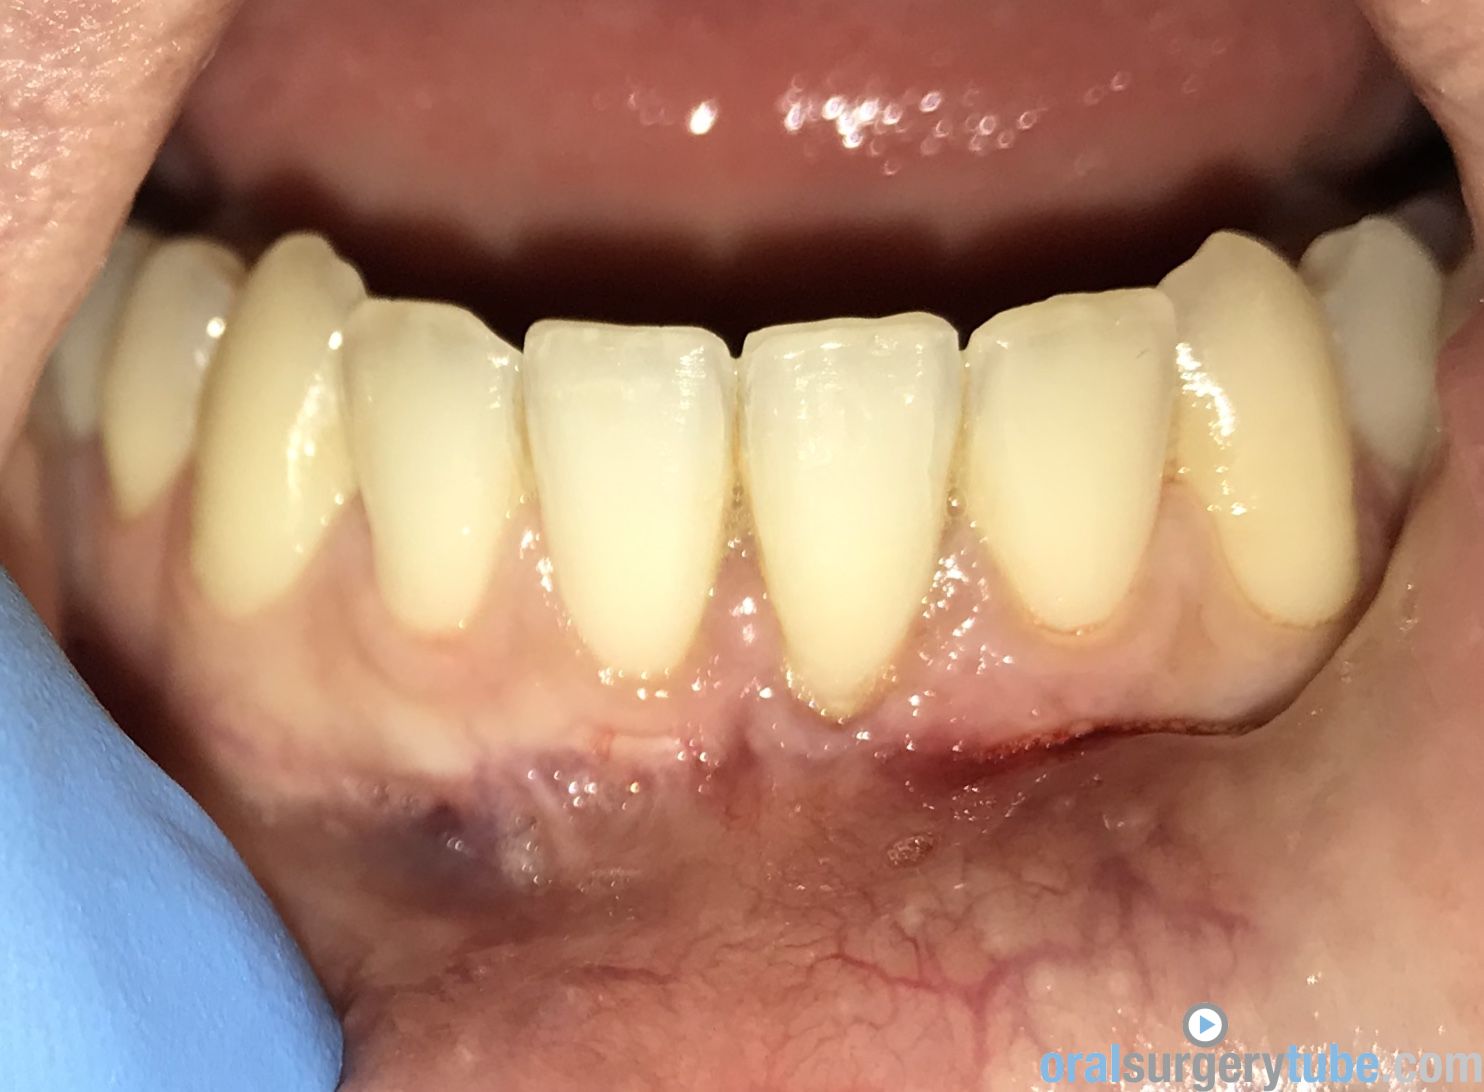

Paciente joven acude para consultar acerca de recesión gingival pieza 31 (clase II Miller). Paciente deja constancia de la importancia de la estética para ella. Hace unos 6 meses, se le realizó cirugía mucogingival con injerto conectivo palatino (la cuál fue fallida, ya que la recesión permanece)... Refiere además cierta molestia al traccionar del labio.

Al movilizar el labio, me transmite la sensación de haber quedado una inserción de fondo de vestíbulo alta... Pienso que podría ser debido a no haber realizado una desinserción muscular al reponer el colgajo coronalmente? (Foto 2). Considero que aún mantiene cierta cantidad de banda queratinizada, pero realmente mínima.

Dado a que se trataría de realizar una "reentrada" o retratamiento (no tengo experiencia hasta la fecha de haber tenido que retratar ningún caso de mucoginigval), agradecería toda opinión acerca de la técnica que más idónea consideréis... Teniendo en cuenta esas posibles adherencias musculares, el biotipo, la demanda estética de la paciente, no sé si lo ideal es tratar con injerto conectivo tipo "técnica bilaminar" y desinsertar la musculatura, o un Injerto de Encía Libre (FGG) y reponer apicalmente la musculatura...

La duda que me surge con el injerto conectivo es si el colgajo me permitiría ser reposicionado coronalmente, teniendo en cuenta esa sensación de "tirantez" actual que describe el paciente. Y la duda de realizarlo con FGG es si conseguiría cubrir la recesión por completo, y si es adecuado para ese solo diente...